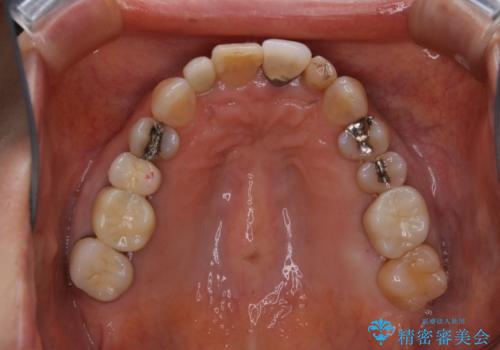

大きな詰め物を被せ物に変えて、歯の破折リスクを減らす

- 以前に異なる種類の材料で継ぎ接ぎ状態で修復されており、隙間のところから虫歯が再発していました。歯の手前側と後方及び内側に亀裂も入っていたため、将来的な虫歯再発のリスク及び歯の破折リスクを最小限にとどめるよう、被せものにて治療を行いました。

- 仮歯1万円・フルジルコニアクラウン7万円(税別)費用は治療当時の料金となります

自費診療で用いられる材料は保険適応の材料に比べて、より精密で適合の良い被せ物作ることができるため、長期的な虫歯のリスクを大幅に減らすことが可能です。